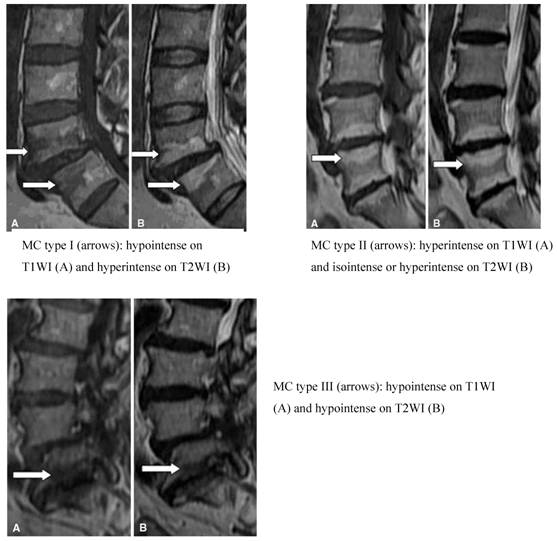

Altered signal strength is often seen in MRIs of degenerative spinal disease in the vertebral end plate and bone under the cartilage. In 1998, Modic et al. [31,32] summarized these changes into groups known as Modic Changes (MCs). The MCs classification is divided into three groups. Type I, also known as the inflammatory phase, is denoted by inflammation of fibrous tissue, low signal intensity on T1W and high signal intensity on T2W imaging. Type II, known as the fat phase, is marked by a large deposition of fat cells in the end plate and the area underneath it, as well as a high signal intensity on T1W and an equivalent or mildly high signal on T2W imaging. Type III, also known as the bone sclerosis period because the bone becomes hardened in the end plate and the area underneath it, is also characterized by low signal intensity in T1W and T2W imaging (Figure 4). Although the etiology has not been fully elucidated, MCs remains a useful parameter set for characterizing morphological changes to the disc. Studies have found that the prevalence of MCs varies from 18 to 62% in patients with chronic LBP, with different ratios relative to asymptomatic patients for each type. Specifically, MCs types I and II were highly prevalent in patients with chronic LBP [34-37] and minimally prevalent in asymptomatic volunteer patients [38,39]. Albert et al. [34] found a strong correlation between MCs and chronic LBP, specifically type I MCs, which reflected the pathological results of changes to the end plate fissure and the subsequent inflammatory response. Kjaer et al. [40,41] reached a similar conclusion in an analysis of 412 40-year old Danish patients. Later, Kuisma et al. showed that type I MCs may be more related to chronic LBP than types II and III. At present, one study has shown a clear relationship between clinical symptoms and MCs on MRI [42]. Another study [43] using discography as a reference standard found that MCs were significantly related to pain of varying consistency. Buttermann et al. [44] found that the sensitivity of MCs for the diagnosis of discogenic pain was relatively high but did not give a specific value. In short, studies have found a close relationship between MC, the pain of DLBP and positive results with discography. The MC parameter has a high sensitivity but slightly lower specificity as an indicator of DLBP.

Figure 4

MC classification (Adopted from Yue-Hui Zhang et al. [33])